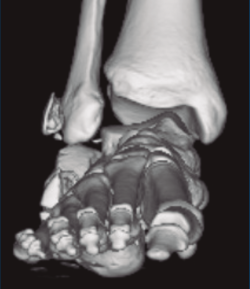

Figura 3. Desplazamiento entre fragmento anteromedial (sustentaculum tali) y posterolateral (tuberosidad).

Se trata de un varón de 19 años que ingresa en reanimación tras precipitarse desde una altura de aproximadamente 10 metros. El paciente presenta una fractura estallido de L3 con afectación del canal medular junto con una fractura del vértice inferior de L4, así como una fractura luxación de calcáneo, asociada a una fractura del maléolo peroneo y del maléolo tibial posterior (Figuras 1 a 6) diagnosticadas mediante TC total body (por eso no se dispone de radiografías simples al momento del ingreso). Como podemos comprobar, se trata de una fractura de doble trazo de tipo hundimiento/depresión de la carilla articular (Figuras 5 y 6).

Figura 4. Luxación fragmento posterolateral.